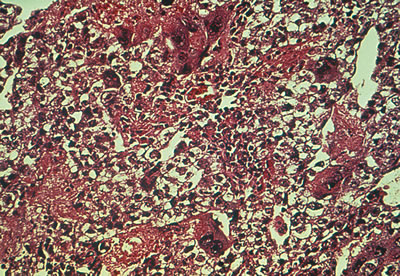

The gross appearance of the yolk sac tumor is classically yellow-red-gray tissue that is soft and friable, with a thin, smooth capsule. Cystic spaces are common, and areas of hemorrhage and necrosis occasionally are found (Fig. 3A). The neoplasm grows rapidly and may be densely adherent to surrounding tissues.

Fig. 3. Yolk sac (endodermal sinus) tumor. A. Yolk sac tumor is classically yellow-red-gray, soft, and friable with multiple cystic areas representing areas of hemorrhage and necrosis. B. A pattern is shown of pleomorphic, poorly differentiated cells with papillary clusters and a pseudopapillary projection with a vascular component within the center (Schiller-Duvall body).

Microscopically the yolk sac tumor exhibits a fairly constant pattern of a loose network of pleomorphic, poorly differentiated cells. These cells have an epithelial appearance in some areas, with papillary clusters thrusting into cystic spaces (Fig. 3B). Extracellular and intracellular round or oval hyaline globules (Schiller-Duval bodies) are a frequent finding.